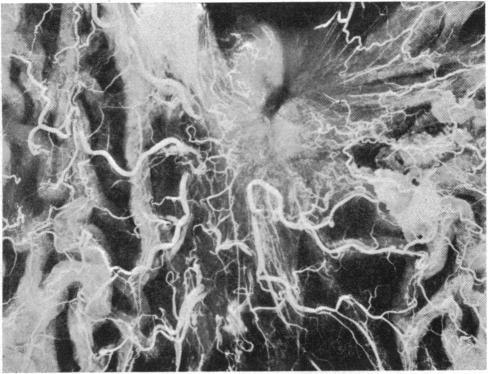

Blood vessels of a gastric ulcer.